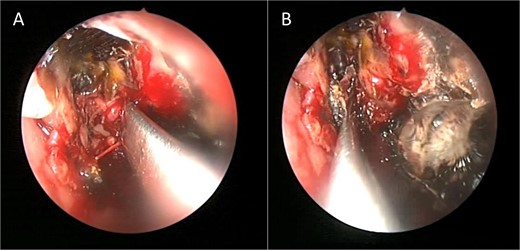

Intra-operative endoscopic maxillary examination (A and B) showing invasive fungal debris.

A 12-year-old young girl with relapsing acute myeloid leukemia presented with fever, headache, and left maxillary facial pain. Her symptoms were associated with blood-tinged nasal discharge. Nasal endoscopic examination showed friable ulcerative mucosa of the left middle turbinate and osteo-meatal complex which raised a clinical suspicion of invasive fungal sinusitis. Thus, a contrast-enhanced CT scan (CECT) (Fig. 3) was necessary which showed enhancing left maxillary sinus opacity suggestive of acute invasive fungal sinusitis. The patient underwent urgent endoscopic medial maxillectomy with removal of invasive fungal debris (Fig. 4) along with debridement of left middle turbinate, medial maxillary wall, and orbital floor. A diagnosis of invasive mucormycosis was confirmed by histopathology. The patient was started on aggressive treatment in the form of intravenous and oral antifungal medications. She was regularly followed up for the next 5 years with no evidence of recurrence.